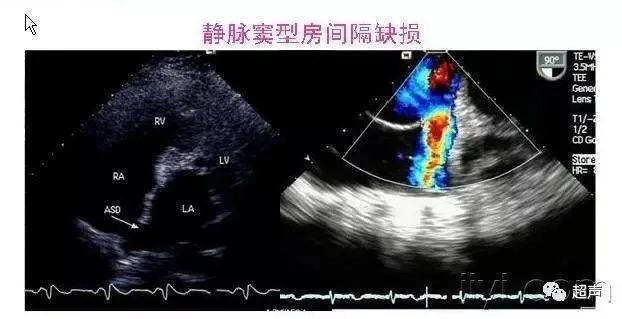

胎儿先天性心脏病都有哪些类型?

预后如何?

先天性心脏病谱系特别广,包括上百种具体分型,症状千差万别,最轻者可以终身无症状,重者出生即出现严重症状如缺氧、休克甚至夭折。

根据先心病能否手术及术后疗效进行综合预后评估,可将先心病分为三型:可根治型、可治姑息型、无法治疗型。

可根治型:指手术几乎或完全矫治,效果满意、预后良好,术后与正常儿童相同或基本相似,如室间隔缺损、肺动脉瓣狭窄及部分法洛氏四联症等。

可治姑息型:指手术难以完全解剖性修复,仅改善生活质量和临床症状,与正常儿童差距较大,如部分病例的右室双出口,部分病例的永存动脉干,重症法洛四联症等。

无法治疗型:指无法进行手术矫治,患儿难以生存或生存质量差,如左心发育不良综合征,右心发育不良综合征,部分病例的单心室,部分病例的三尖瓣下移畸形等。

由于先天性心脏病已连续多年位于我国出生缺陷的第一位,因此,建议每一位孕妈妈在孕期都要常规做一次胎儿心脏系统超声检查,早诊断、早评估、早治疗。